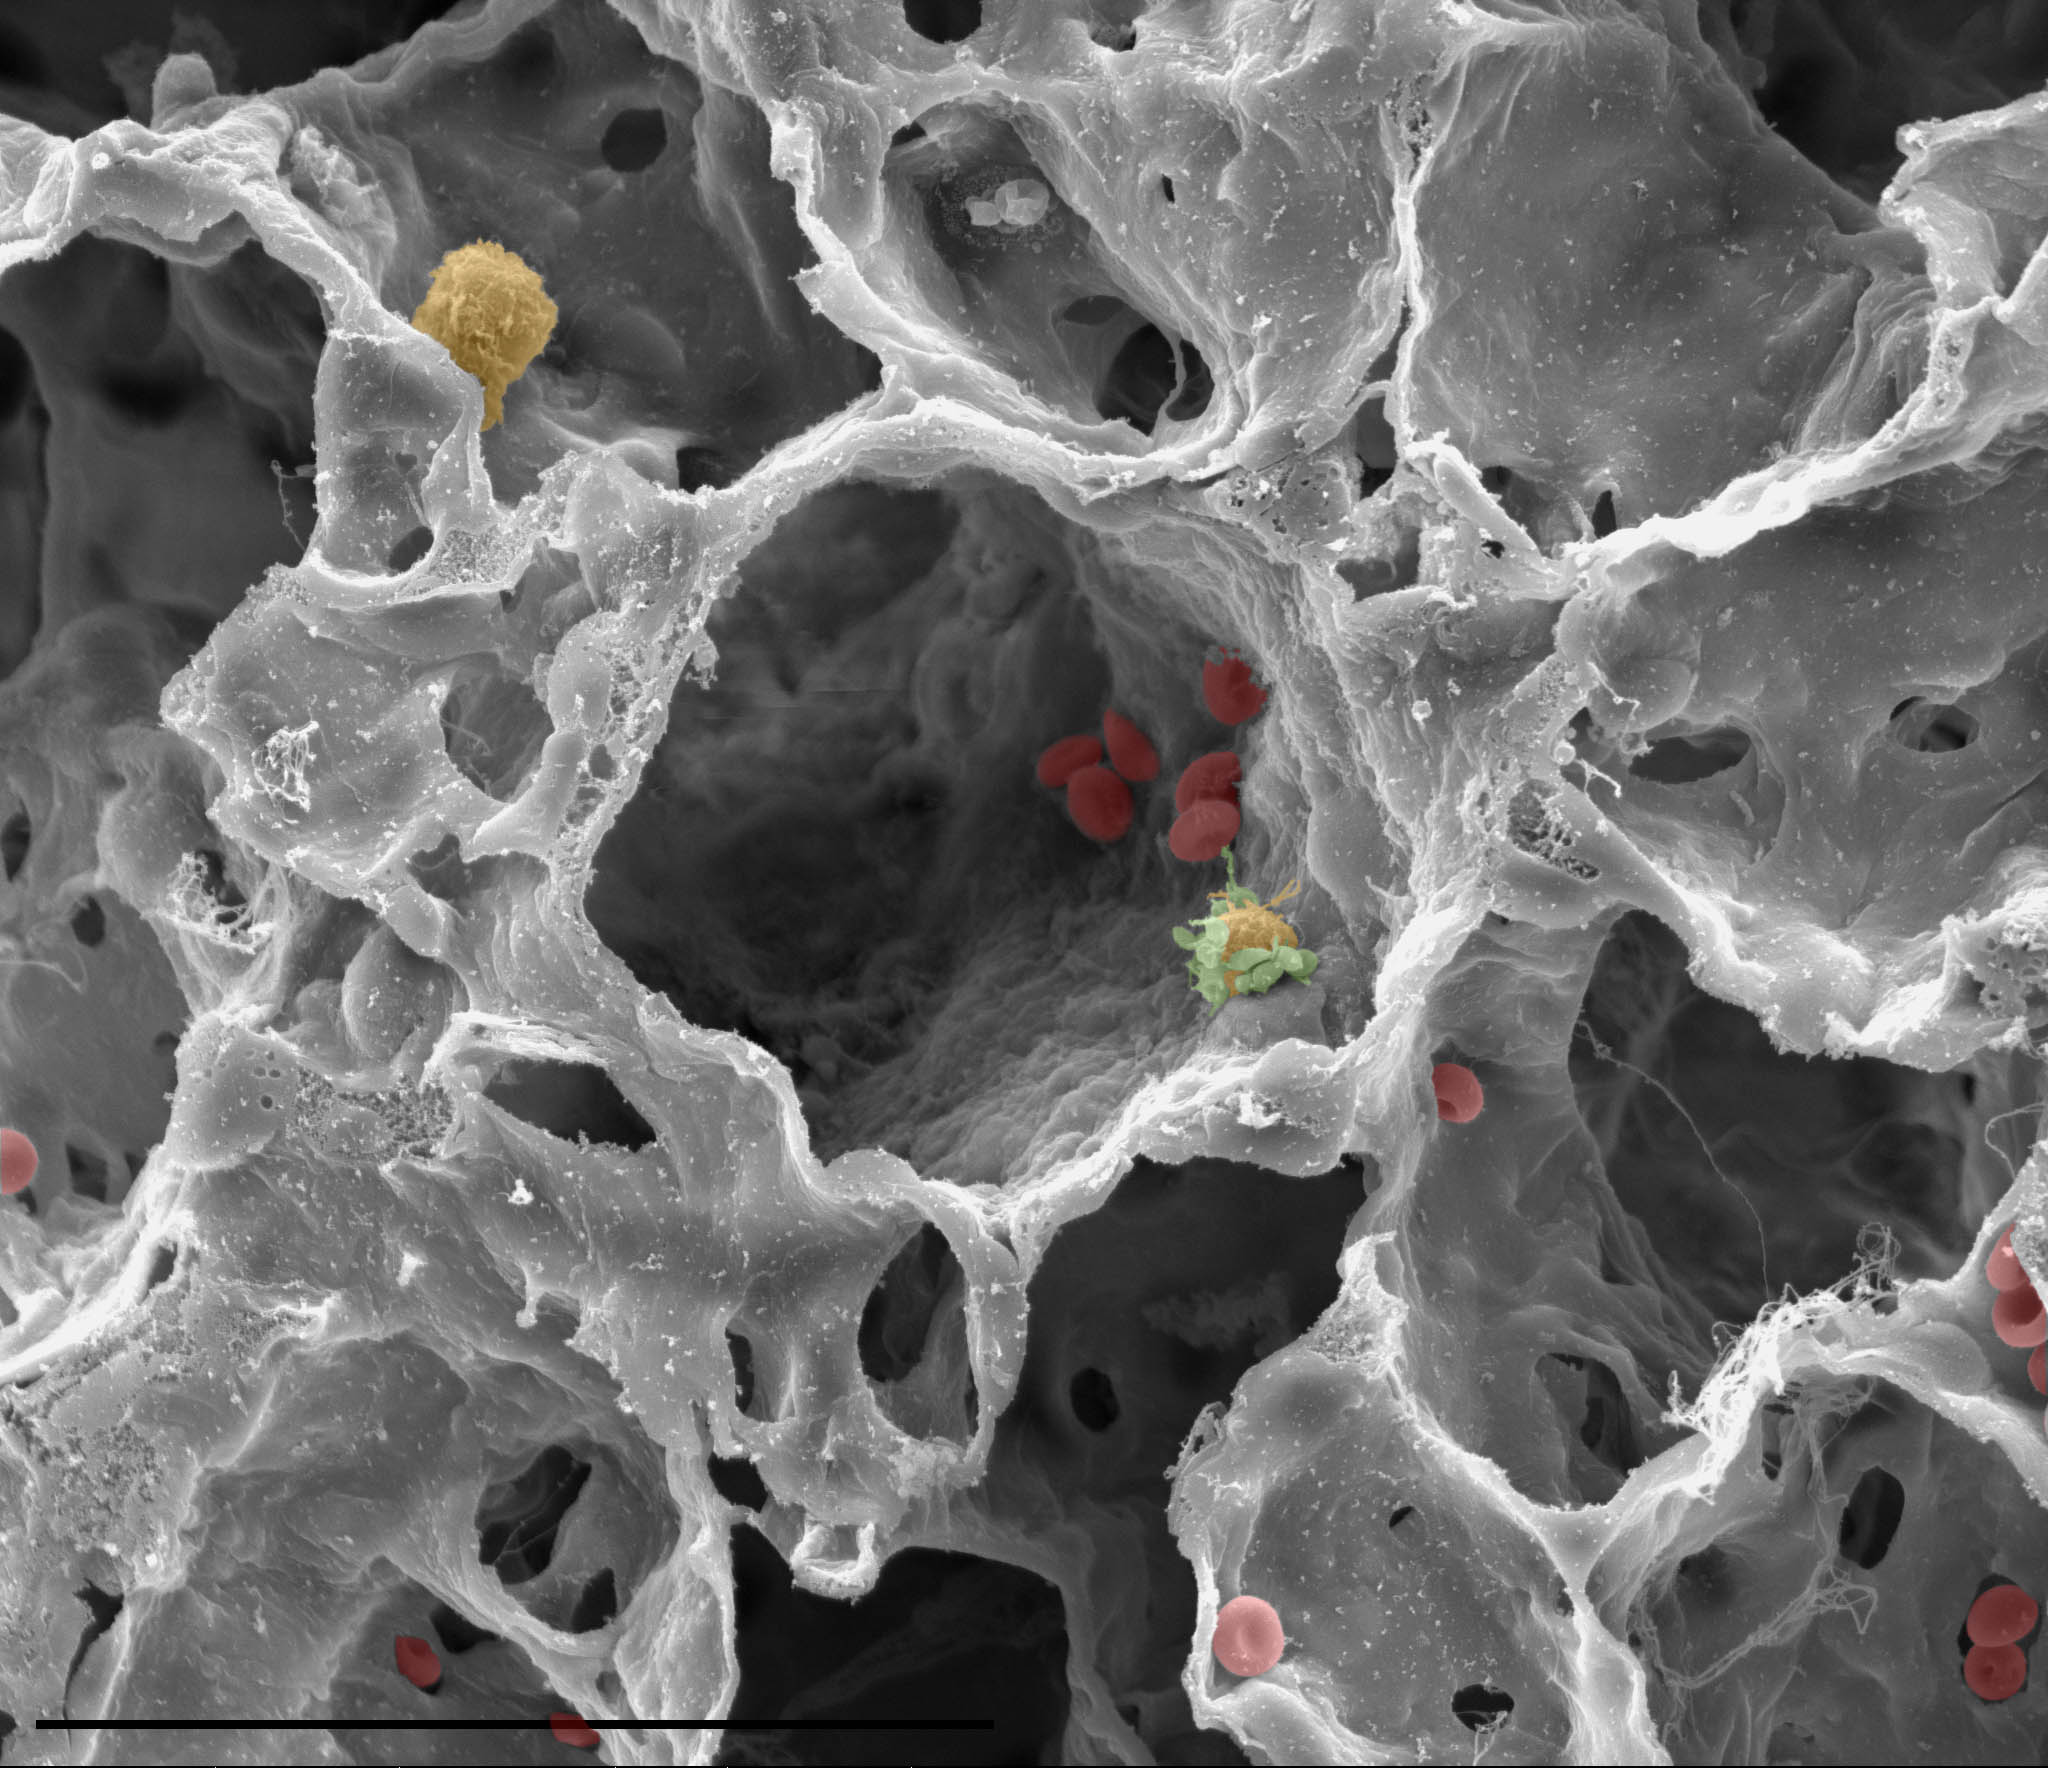

AAT is produced by the liver, released into the bloodstream where it travels to the lungs. There AAT protects the lung alveoli from a powerful enzyme called neutrophil elastase. The physiological role of neutrophil elastase is to protect the same alveoli from infections and harmful irritants; the enzyme then gets inactivated by AAT. However in the absence or lower abundance of AAT, elastase will attack the lung tissue itself, causing irreversible damage.